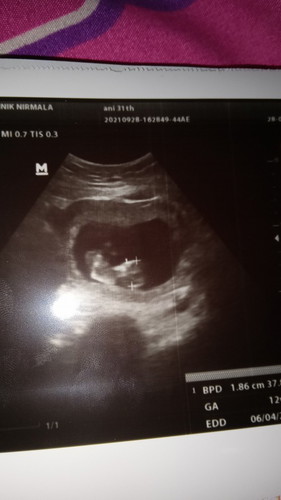

Lihat beby